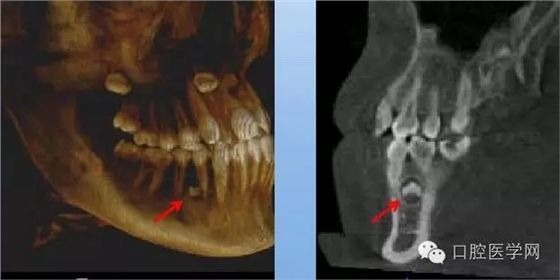

4.阻生牙

最常見(jiàn)于下頜第三磨牙

X線表現(xiàn):確定阻生牙的位置;確定阻生方向;牙根數(shù)目和形態(tài);阻生牙有無(wú)齲齒和根尖情況;與第二磨牙的關(guān)系;與下頜管的距離和磨牙后間隙的大小。